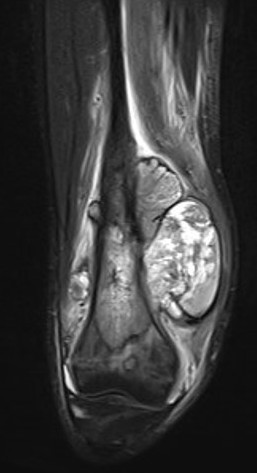

MRI

Evaluate

i) Soft tissue component

ii) Involvement of neurovascular bundle

iii) Marrow extent of tumour

- helpful in determining appropriate resection level

- satellite lesions - metastasis within reactive zone

iv) Identify skip lesions

- metastasis outside reactive zone

- sagittal and coronal images of the entire bone

v) Joint involvement